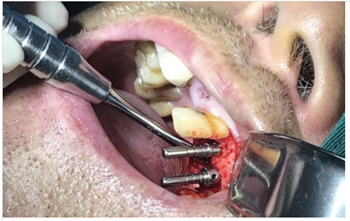

使用種植導(dǎo)板專用手術(shù)器械完成種植位點(diǎn)逐級(jí)備洞

進(jìn)行精準(zhǔn)測量

植體置入